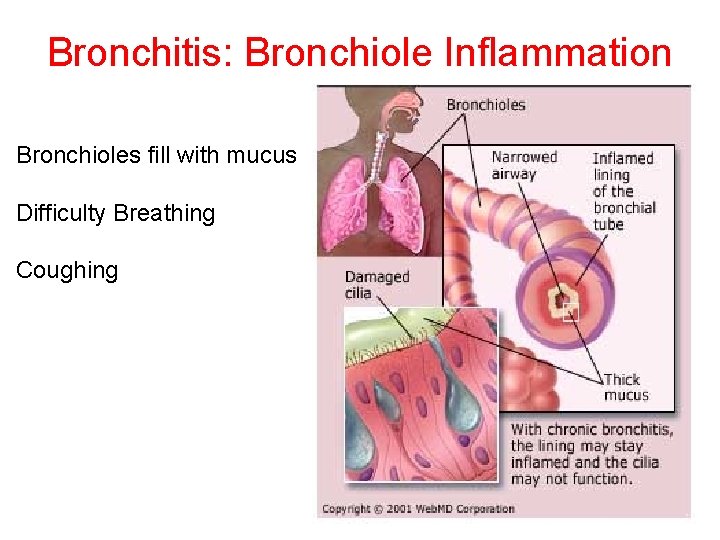

Bronchitis: Bronchiole Inflammation Bronchioles fill with mucus Difficulty Breathing Coughing